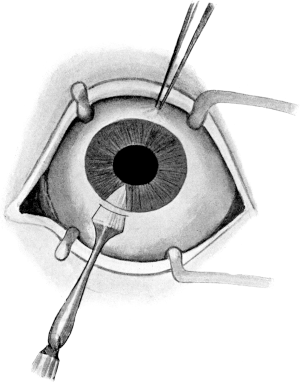

| 78. | Cataract Extraction | 183 |

| 94. | Lens Extraction | 196 |